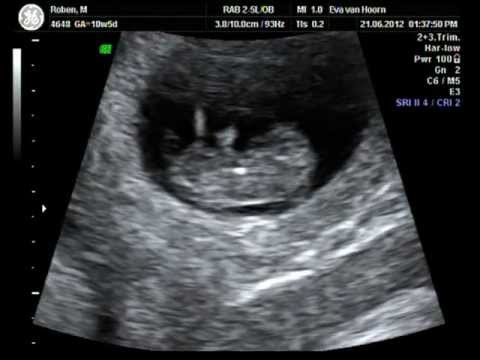

waahhh ik ben zo blij vandaag mijn eerste echo van mijn baby(s). ik doe een gemakkelijke broek en trui aan en stap in de auto en rijd naar het ziekenhuis. Ik neem stijn expres niet mee want wil de echo aan hem als verrassing geven voor valentijnsdag. eenmaal in het ziekenhuis mag ik meteen doorlopen. de vrouw doet een koud goedje op mijn buik. de echo wordt gemaakt en ze zegt gefeliciteerd je hebt een tweeling. ik glunder helemaal. daarna wordt de foto afgedrukt en rijd ik weer naar huis. ik pak de foto in in cadeaupapier en leg ze bij het chocolade hart wat ik eerder had gekocht. ik loop naar divas stal en omhels haar.